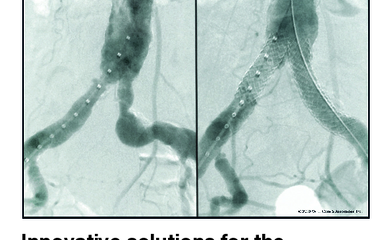

Educational Supplement: Vascular News Europe Innovative solutions for the treatment of complex AIOD using GORE® VIABAHN® Endoprosthesis and See more